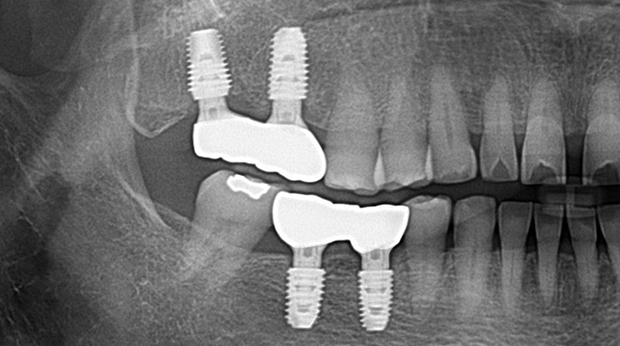

의식하진정법(수면마취)/임플란트

임플란트와 사랑니 발치는 외과적 시술로 잇몸을 절개하는 외과적 시술은

짧으면 짧을 수록 시술 후 붓기와 통증이 최소화됩니다.

치과의사 경력 14년차 구강외과 전문의가 빠르고 안전하게, 아프지 않게 수술해 드립니다.